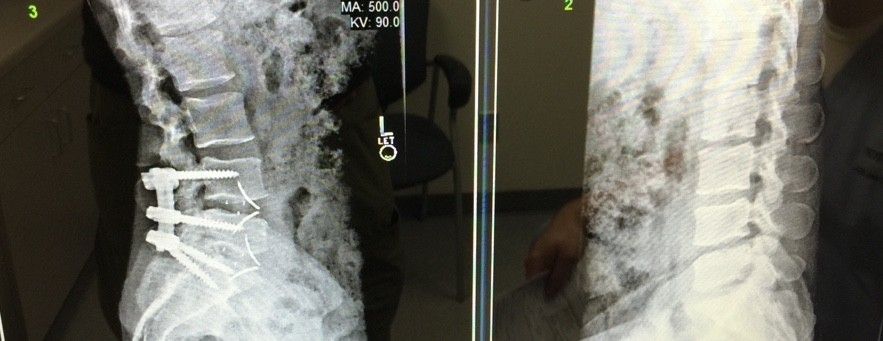

Here's my new titanium hardware. Should I compare it to the material that it replaced?

Power to the Metal! Damn, those screws look huge, though.Here's my new titanium hardware. Should I compare it to the material that it replaced?

Yeah they're pretty gnarly. I finally get to walk around without that damn uncomfortable brace now. Whew, that sh** has been rough!Power to the Metal! Damn, those screws look huge, though.